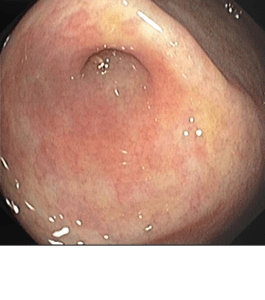

- Preparación y Posicionamiento: El paciente se posiciona de manera adecuada para la inserción del colonoscopio, que permite una visión directa de la hemorroides.

- Colocación de las Bandas: Usando el colonoscopio, se colocan pequeñas bandas de silicona alrededor de las hemorroides. Estas bandas cortan el suministro de sangre a las hemorroides, haciendo que se sequen y eventualmente se desprendan.

- Indicaciones: La ligadura de hemorroides con bandas está indicada para hemorroides internas que causan síntomas como sangrado, molestias o protrusión. Puede ser recomendada cuando otros tratamientos más conservadores no han sido efectivos.